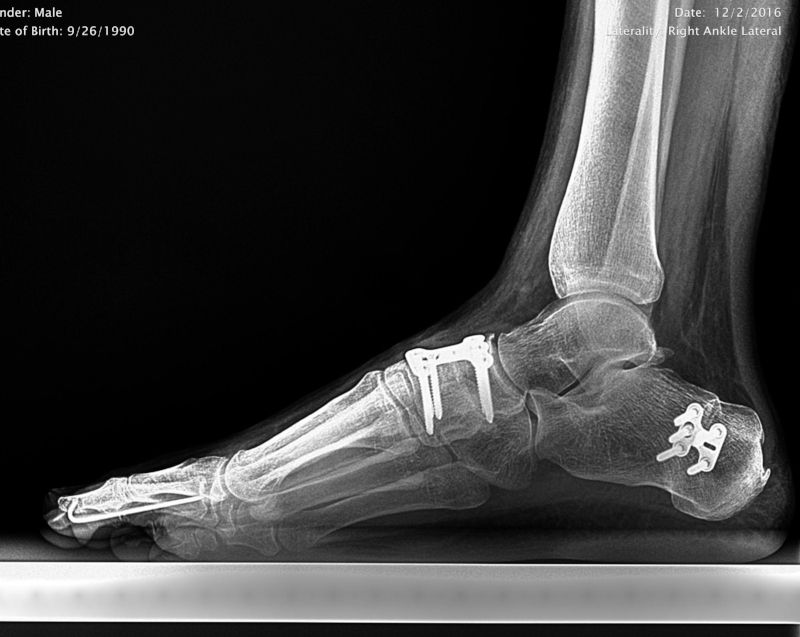

Flat Foot